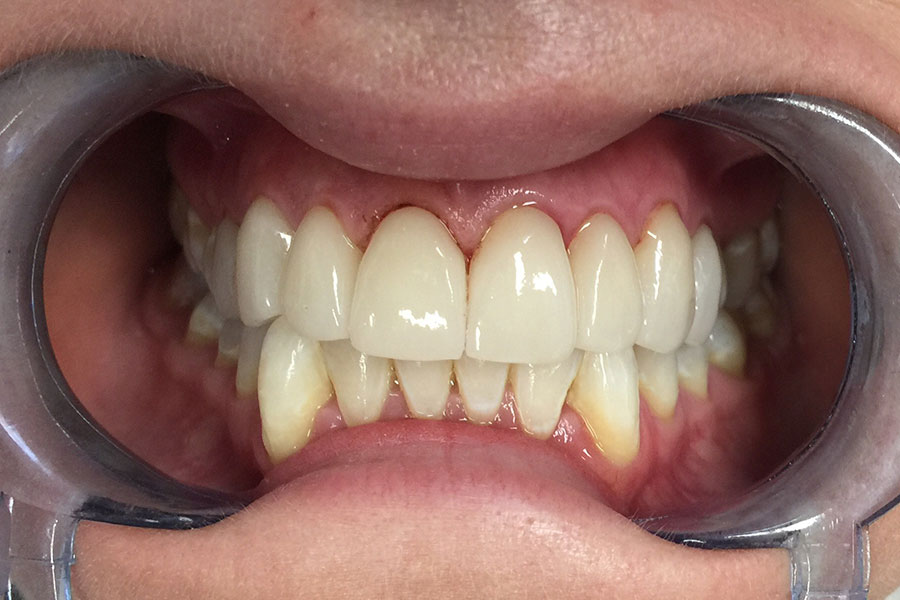

The following cases had stained and failing white fillings. Interestingly one person even had very old gold inlays in their front teeth.

They were replaced with esthetic ceramic veneers. As seen in these images changes to shape and size within limits can also be achieved along with the color.